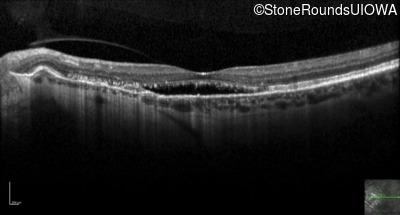

Optical Coherence Tomography - Right - 20/25 +2 sc

Exemplar / OCT Stack

OCT Stack